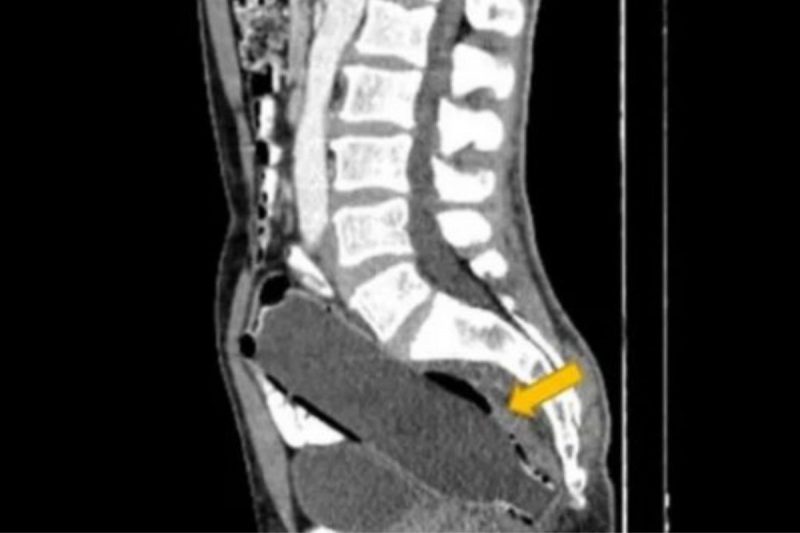

Homem estava com uma garrafa alojada no intestino – Foto: ReproduçãoHomem estava com uma garrafa alojada no intestino – Foto: Reprodução

Após uma tomografia, os médicos constataram uma garrafa da 19 centímetros, cujo fundo estava perto de entrar no intestino grosso do paciente. O caso foi relatado na revista Clinical Case Reports“.